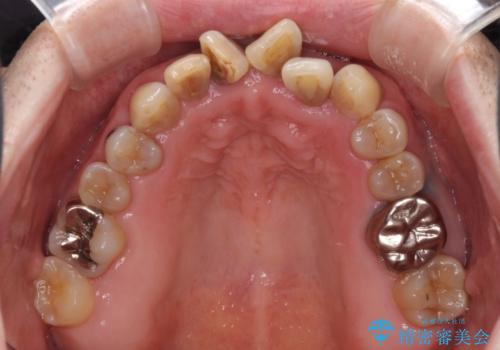

上顎の狭窄歯列 インビザラインによる拡大矯正

- 前歯の叢生と臼歯のクロスバイトを気にして来院された患者様です。

急速拡大装置による上顎の側方拡大を行い、その後はインビザラインより歯列を改善することとしました。

20代後半以降の男性は上顎骨の側方拡大処置の成功率が低く、今回も骨を拡大することができませんでした。

しかしながら、歯列を側方に拡大することができ、その後はインビザラインにて叢生を解消することができました。